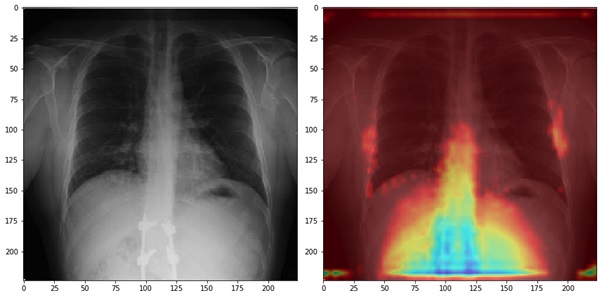

La imagen corresponde a un paciente con Covid-19: en la izquierda se aprecia la radiografía de tórax como la genera el equipo radiológico, y a la derecha podemos apreciar la imagen procesada por el estudio.

Para la investigación, RedSalud ha incorporado cerca de 1.500 radiografías anónimas para que un sistema de inteligencia artificial pueda “aprender” a diferenciar un paciente con Covid-19, de un paciente sano o de un paciente con otra patología. Con esta información, el equipo de investigación ya ha conseguido llegar a un sistema que permite detectar casos positivos de Covid-19 con una precisión y sensibilidad de entre 80% a 90%.